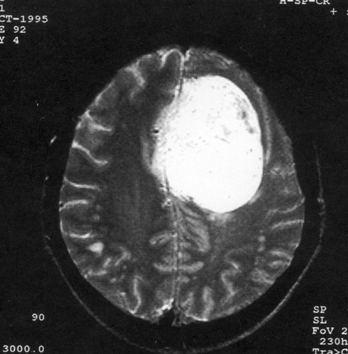

问题 病历摘要:??患者女性,37岁。大便时突起炸裂样头痛3小时,伴喷射样呕吐。既往体健。体检:T37.5℃,BP145/90mmHg,R20次/分,P85次/分。神志清楚,颅神经检查无异常,颈强直,克、布氏征(-),四肢肌力、肌张力正常,病理征(-)。 目前治疗颅内动脉瘤的主要方法有哪些?

选项 A.r刀 B.开颅动脉瘤夹闭术 C.开颅载瘤动脉夹闭及动脉瘤孤立术 D.开颅动脉瘤包裹术 E.血管内动脉瘤栓塞术 F.X刀 G.动脉瘤颈结扎术 H.颈动脉结扎术

答案 BCDE